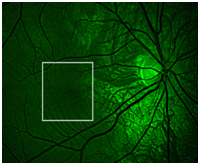

3. Slit lamp examination: RIGHT, LEFT Iris transillumination (Figure 1). She was blonde, did not tan and showed mild photosensitivity. Fundus examination revealed bilateral foveal hypoplasia (Figure 2&3). An OCT of the macula was done and this confirmed bilateral foveal hypoplasia (Figure 4−6).

Figure 2 Red Free fundus Photographs of the Right and Left eye showing Foveal hypoplasia.

Figure 3 Foveal hypoplasia under higher magnification.